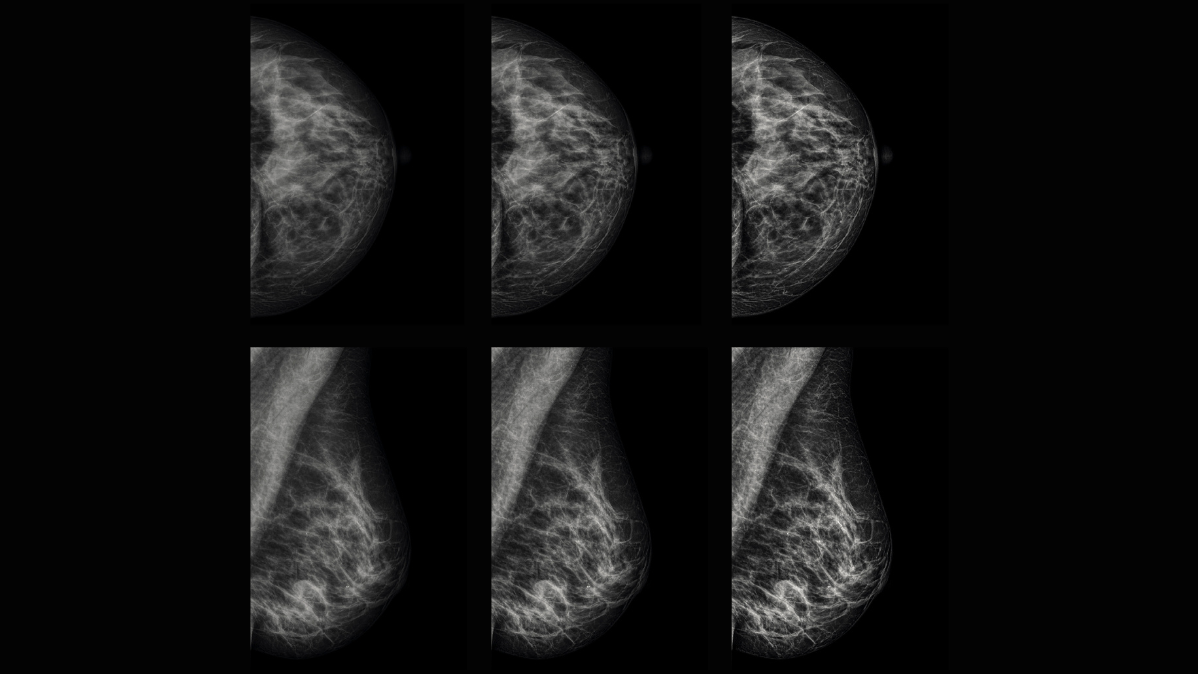

Obrazy Kliniczne Planmed Clarity 2D